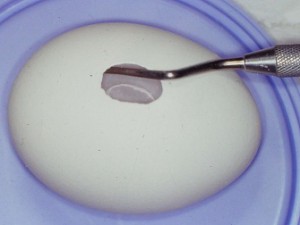

明日は久しぶりにサイナスリフトのオペが入っている。しょっちゅうあるわけではないので、オペ前には感覚を戻すために、必ず生卵で練習している。生卵で100発100中うまくいけば、臨床では100パーセントうまくいくという話もあるが、臨床の方がいろんな制約があって(出血するとか、見ずらいとか)、結構大変だ。高速回転の昔ながらの機械で、生卵の中の膜を破らずに窓開けをする。生卵の殻が実際の臨床では顎の骨に相当する。最近はピエゾサージェリーなる超音波の機械がはやってきて窓開けも楽ちんになったという話をよく聞く。今日バイトに来てたN先生に聞いたら、「医科歯科大インプラント治療部ではピエゾから昔のやり方に戻った」とのこと。やはり手の感覚に勝るものは無いのか?2002年にミシガン大学に行ってまで覚えたこの手術。患者さんごとに解剖学的構造が異なるので、ちょっと慣れたからと言って舐めてはかかれない。前の晩は妙に緊張する。さあ早く寝よう。

生卵でサイナスリフトの練習